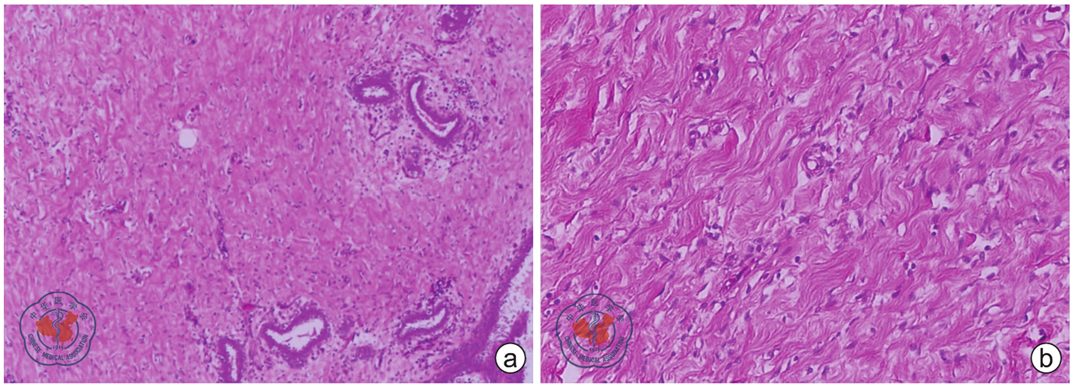

图3 乳腺及副乳腺假血管瘤样间质增生患者左腋窝肿块镜下表现 a图所示肿块镜下边界不清,梭形细胞增生伴致密胶原沉积,穿插于乳腺小叶间及小叶内(HE ×100);b图所示梭形细胞形态温和,排列成大小不等、不规则裂隙状结构,未见明显核分裂象(HE ×200)